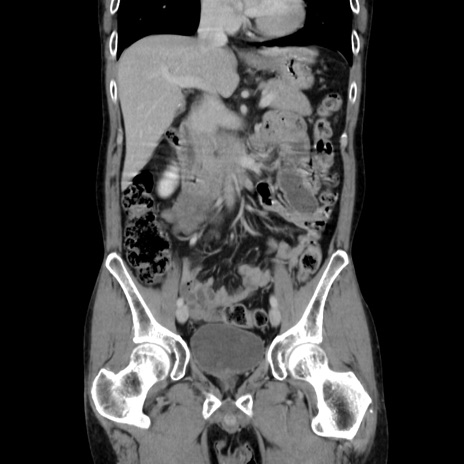

症例37(冠状断像)

【症例】40歳代 男性

【主訴】腹痛

【現病歴】4時間ほど前に電車に乗車中に臍部上より腹痛出現。徐々に増悪し起立困難となり、救急外来受診。生ものは数日食べていない。今朝お雑煮を食べた。

【身体所見】BT 36.8℃、BP 117/84mmHg、HR 91/min、SpO2 97%、苦悶様、腹部:臍上部広範囲圧痛あり、反跳痛±

【データ】WBC 8100、CRP 0.03